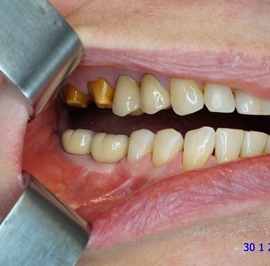

Bezzębie całkowite górne. Początkowo wykonane na mieście mosty całoceramiczne wydawały sie sukcesem, ale po roku pojawiły sie obrzęki i krwawienie z dziąseł. Pacjentka zgłosiła się do leczenia. Usunięto wszystkie zęby w szczęce. Sterowana regeneracja tkanek kości wyrostka, modelowanie kształtu i objętości tkanek miękkich, mosty porcelanowe przykręcane do implantów. Zadowalający wynik anatomiczny i estetyczny.